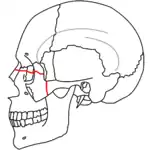

A principios del siglo XX, René Le Fort trazó ubicaciones típicas para las fracturas faciales, éstas ahora son conocidas como I, II y III fracturas de Le Fort (derecha).[5][2][6]

La fractura de Le Fort tipo I, también llamada Guérin o fractura del maxilar horizontal,[7][8] implican al maxilar superior, separándolo del paladar.[9]

La fractura de Le Fort tipo II, también llamada fractura piramidal del maxilar,[7][10] cruza los huesos nasales y el reborde orbitario.[9]

La Fractura de Le Fort#Lefort III, también llamada disyunción craneofacial y fractura facial transversal,[7][11] cruza la parte delantera del maxilar superior e implica al hueso lacrimal, a la lámina papirácea, y a la cavidad orbitaria, y a menudo implica al hueso etmoides,[9] es la más grave.[12] Las fracturas de Le Fort, que representan del 10% al 20% de las fracturas faciales, a menudo son asociadas con otras lesiones graves.[9]

Le Fort hizo sus clasificaciones basadas en el trabajo con cráneos de cadáveres, y el sistema de clasificación ha sido criticado por impreciso y simplista ya que la mayoría de las fracturas del tercio medio facial implican una combinación de las fracturas Le Fort.[9] A pesar de que la mayor parte de las fracturas faciales no siguen los patrones descritos por Le Fort de forma precisa, el sistema todavía se utiliza en la clínica para clasificar las lesiones.[13]